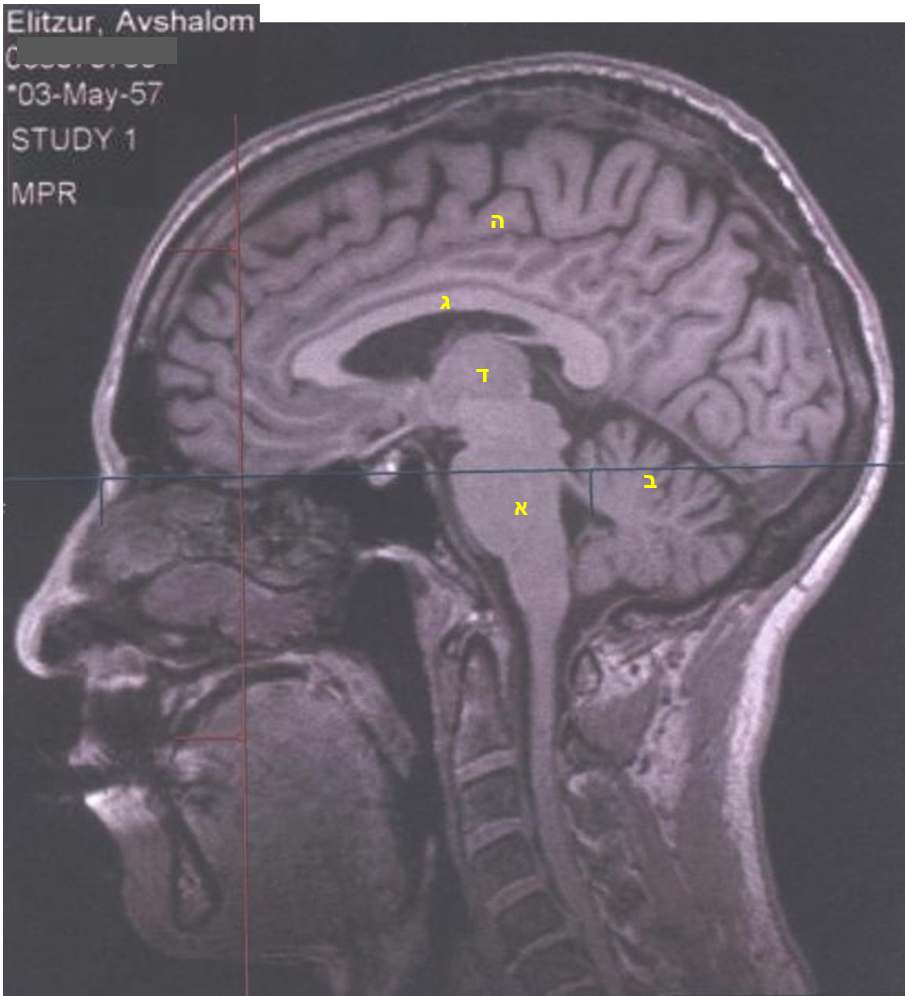

אז כאן בתמונה אתם יכולים לראות (מלבד סתימות שורש, שינויים בע"ש צווארי ושאר סימני גיל) את השכבות האבולוציוניות האלה. בואו נתחיל.

במרכז התמונה (א) גזע המוח שלי, יורד כלפי מטה ונמשך כחוט השדרה. זה החלק העתיק ביותר האחראי לפעולות הווגטטיביות של הגוף, כמו מחזור הדם, הנשימה והעיכול. בעורף, מימין לגזע המוח (ב), נראה הצֵרֵבֶּלוּם (מוחון). זהו מעין "מוח שני" לצד הצֵרֶבְּרוּם (המוח הגדול, מעליו בכל הגולגולת), והוא אחראי לקואורדינציה ולדיוק פעולות שכבר נלמדו ע"י המוח הגדול. מעל לגזע המוח נמצאת מערכת איברים הקרויה בשם הלא מדויק המערכת הלימבּית (גובלתית) ובה ההיפוקמפוסים, זוג איברים דמויי שופר האחראים על תחילת מנגנון הלמידה. בקצותיהם יושבים שני גרעיני האמיגדלה, האחראיים למגוון תפקודים מעניינים מאוד, מאגירת זיכרונות טראומטיים, זיהוי פרצופים, ועד לשלישיית ה-FFF המפורסמת: פחד, לחימה בריחה, שעליהם צריך להוסיף עוד F למילה גסה, כי זה גם מה שקורה בהתעוררות המינית. אלה כמובן חוויות שונות מאוד, אבל בכולן פועל אותו מנגנון הכנסת הגוף למצב פעולה חזק, מה שיוצא לפעמים משליטתנו במקרים של התפרצות זעם, פאניקה, או ההיפך, היסחפות לאקט מיני אסור. לא ייאמן, אבל כולם נתונים לשליטת הגרעין הקטן ורב-העוצמה הזה, האמיגדלה.

ה-MRI הזה מראה חתך רוחב אמצעי, ובו ניכר (ג) הגרעין הזנבי, המבנה הבהיר דמוי הקשת מעל לגזע המוח. הוא אחראי לממסר בין קליפת המוח למערכת התנועה, ומצד שני לעיכוב ומניעת פעולות, וכן למערכת הגמול. מתחתיו חתך רוחב של התַלַמוּס (ד), שהוא מעין מרכזייה המעבירה את הקלט החושי מהעיניים והאוזניים אל אזורי הראייה והשמיעה.

השכבה שמעליהם (ה), מרובת הפיתולים, היא קליפת המוח וכפי שאתם רואים היא המפותחת ביותר בפרימאטים ובעיקר באדם ומהווה את מרבית המוח הגדול. כאן מתבצעים עיבוד המידע המגיע ממרכזי הראייה, השמיעה וההרחה, כאן מתבצעים החשיבה והדיבור וקבלת ההחלטות. בחתך הרוחב הצידי הזה ניתן לראות את האונות האמצעיות של קליפת המוח: העורפית, הקודקודית והמצחית, ולכל אחת תפקיד מכריע משלה.